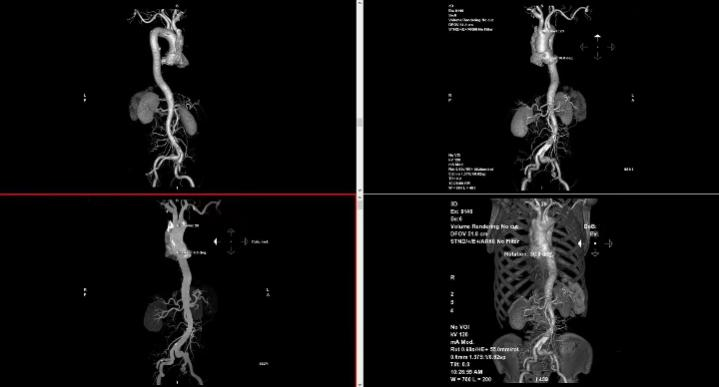

我们的服务项目涵盖了全身各部位的影像检查,包括但不限于:头部、颈部、胸部、腹部、盆腔、四肢等部位的CT、MRI、DR等检查。我们还提供特殊的影像检查服务,如血管造影、MR多功能成像等。例如:

血管造影: